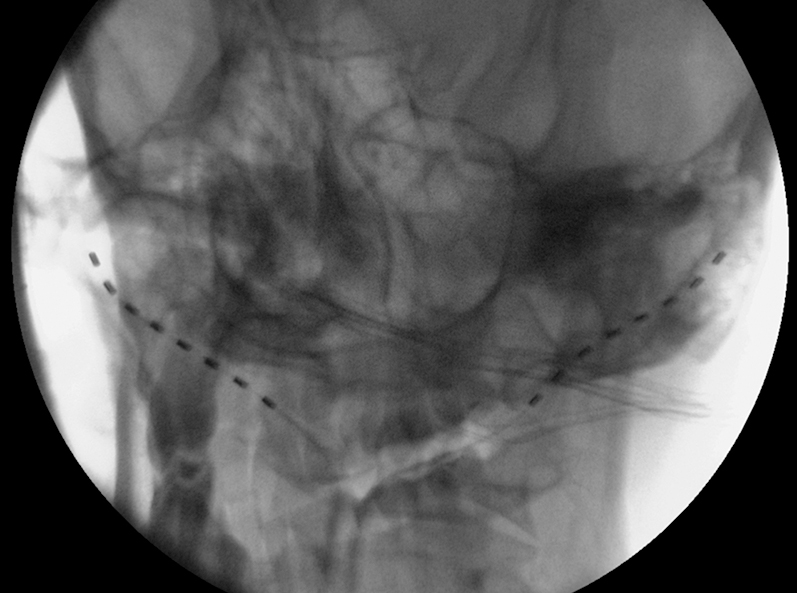

A sterile disposable needle with peel-away sheath, was presented by Shaw et al. [28], applied to peripheral field stimulation trial for low back pain syndrome. With this in mind, we decided to use an Introducer Needle with a T-Peel sheath 8,255 cm length, 17 GA (Avanos Medical, Inc. Alpharetta, GA, USA) (Figure 3). We used the same access selected for the initial implantation, at the C1C2 level, dissecting the planes until we found the anchor corresponding to the left electrode. Gentle removal of anchor, was done using anchor removal tool, and also any remaining suture material that was securing the anchor. The tunnelled portion at the cranial (occipital) level was pulled out. Using the introducer needle, performed an X-ray-guided puncture from the incision to the left mastoid process. Once located, the needle and dilator were removed, the cannula was left in place and the lead was introduced through it. Once verified the appropriate location of the electrode, with a simultaneous movement the cannula was pulled back and stripped, while a push pressure was firmly maintained on the inserted lead, to avoid during the maneuver necessary to remove the cannula, lead’s mobilization from the intended position. The final position of repositioned left lead is shown in Figure 4.

Fluoroscopic image after left lead revision.

The whole system was then tested and confirmed by the patient to be in satisfactory working condition. The lead was then anchored for avoiding dislodgements; layered wound closure with absorbable suture and skin closure with intradermal synthetic absorbable suture, were completed. The patient was transported to recovery and discharged one day after from the hospital. The patient was seen in the office 10 days and six months after the procedure with no complications and total satisfaction with the result.